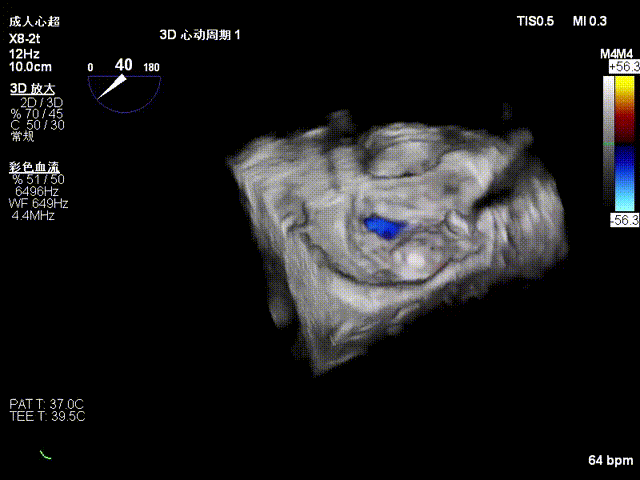

第二枚瓣膜夹植入于P2残余脱垂处